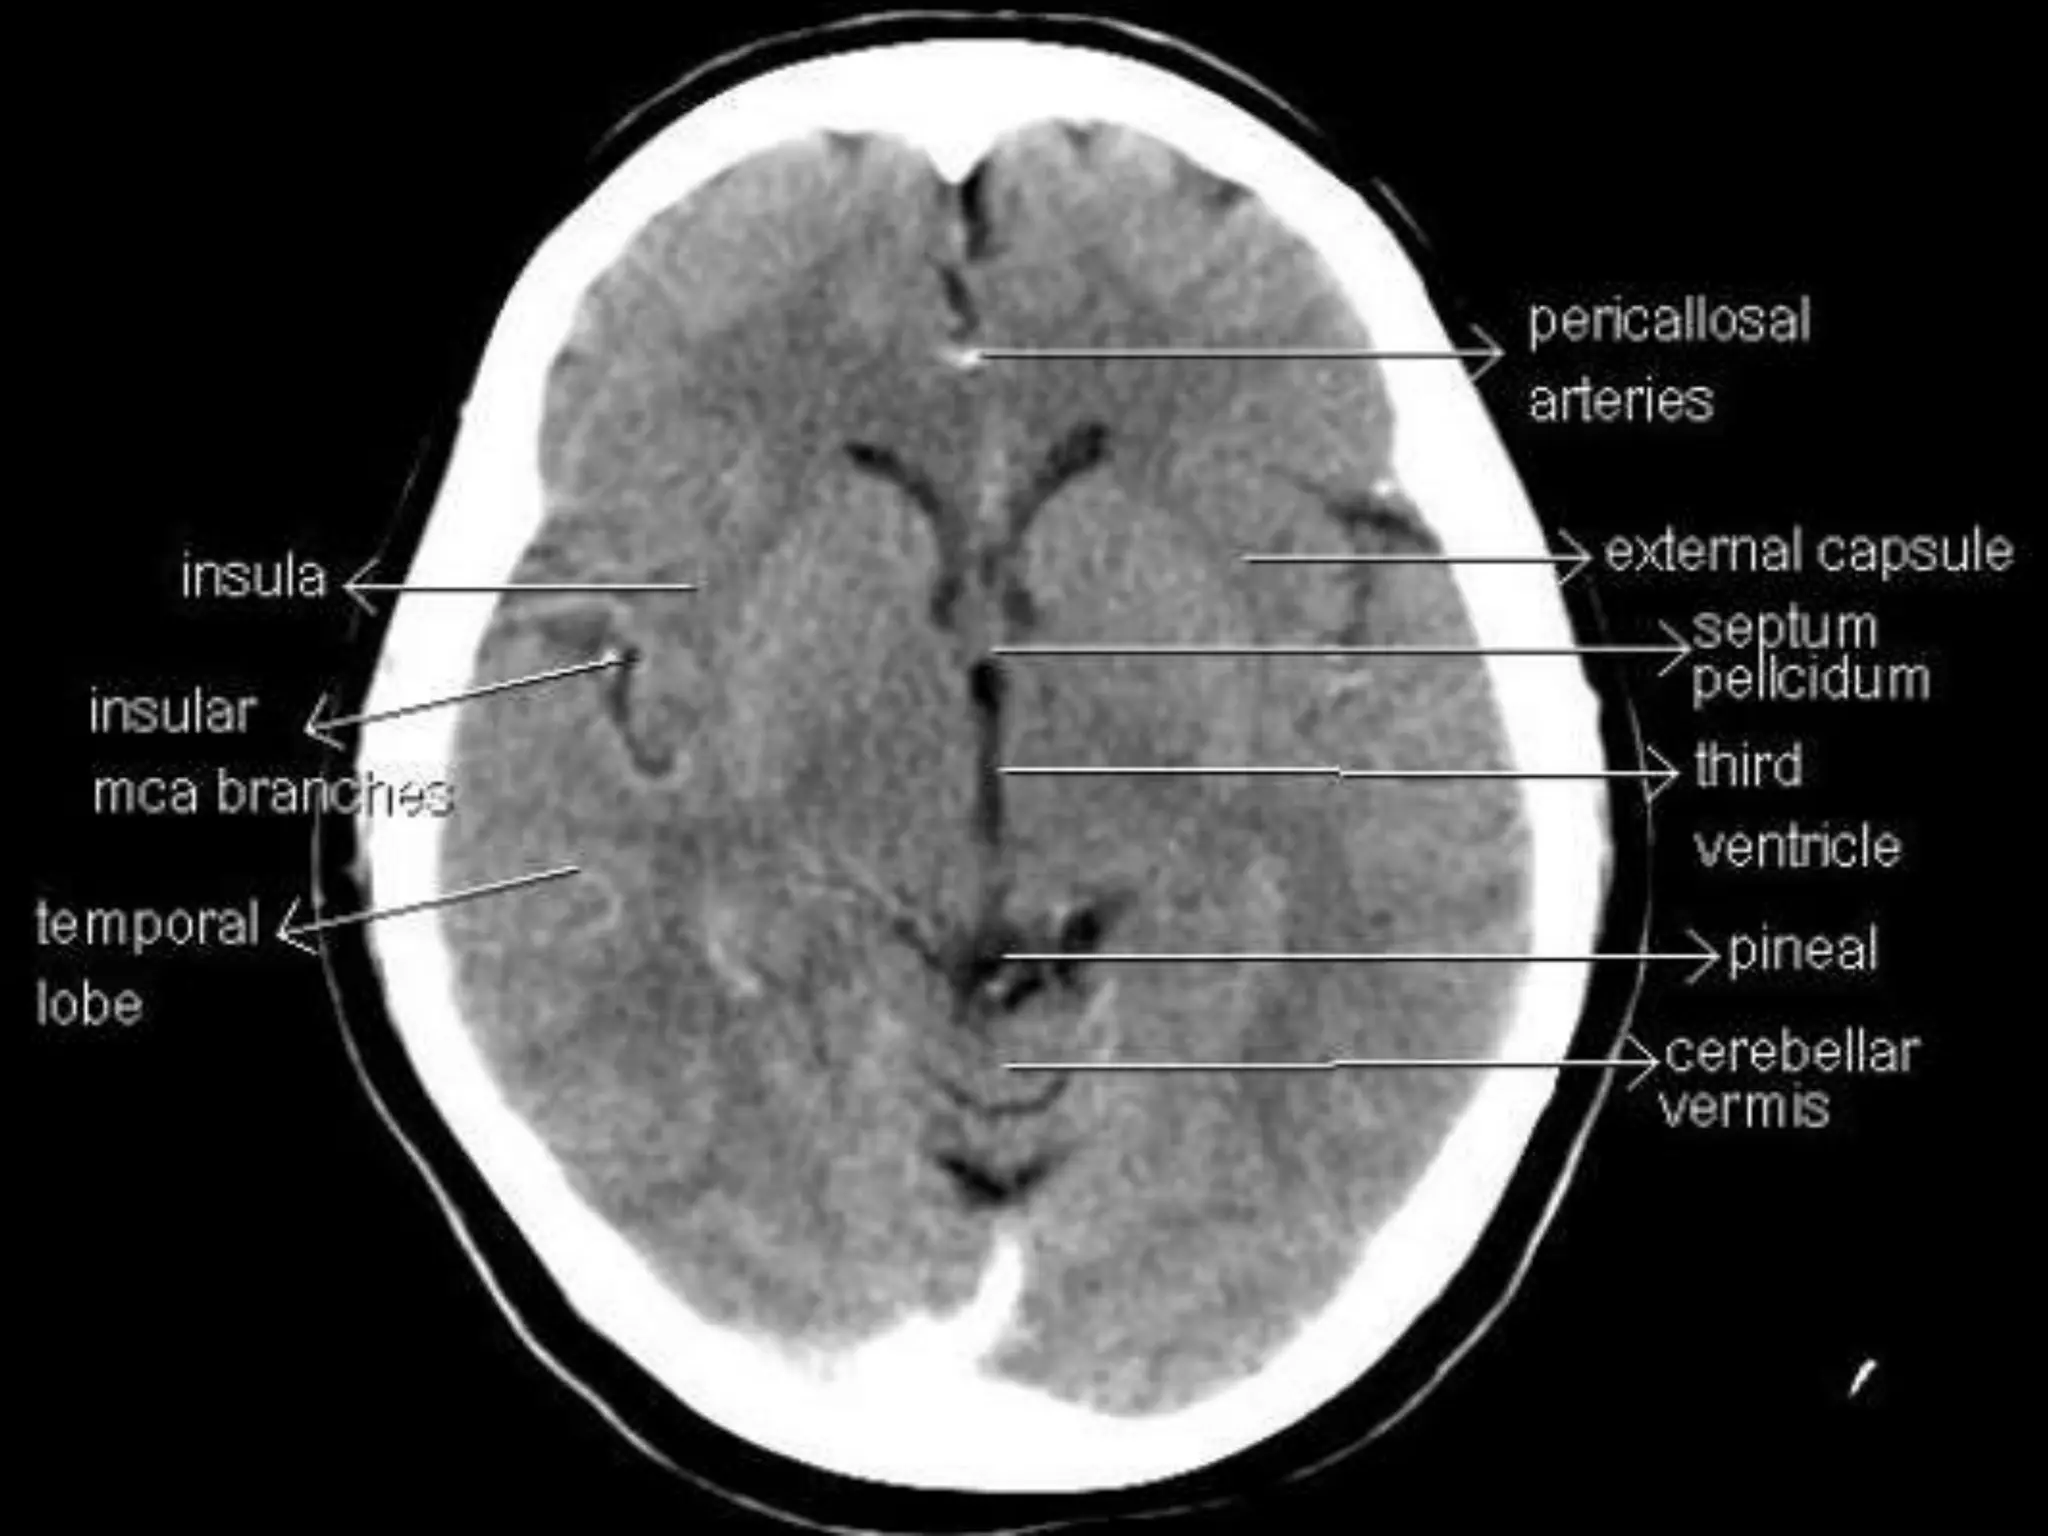

Sectional Anatomy: NormalAxial CT and MRI Anatomy. On CT and MR scans, the brain has been briefly viewed in infratentorial and supratentorial sections, as described below. CT scans are performed with a 15- to 20-degree angulation to the canthomeatal line at 8-mm increments. MRI scans are generally obtained parallel to the AC-PC line in the axial plane with 6-mm slice thickness. Using the sagittal view, the coronal sections are acquired parallel to the brain stem, and the sagittal sections are obtained perpendicular to the axial section. On MRI studies, cranial nerves IX and X can be demonstrated at this level because they emerge from the postolivary sulcus. The posterior aspect of the cerebellar hemispheres is outlined by the inferior portion of the cisterna magna.